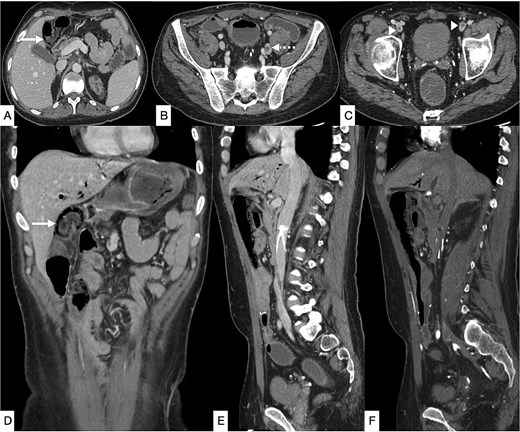

Three months later, the patient re-presented with severe right iliac fossa pain radiating to the left abdomen, associated with fever and clinical peritonism. Laboratory evaluation again demonstrated metabolic acidosis, leukocytosis, and elevated inflammatory markers. CT of the abdomen demonstrated pneumatosis intestinalis in the terminal ileum adjacent to the ileocolic anastomosis, together with new thrombi in the left common iliac and bilateral femoral veins (Fig. 3).

Contrast-enhanced CT of the abdomen and pelvis in axial (A–C), coronal (D), and sagittal (E, F) planes showing diffuse pneumatosis intestinalis just proximal to the previous anastomotic site (bold arrow), consistent with bowel ischemia. New thrombi are identified within the left common iliac vein (dashed arrow) and bilateral common femoral veins (arrowhead). Mild residual pneumobilia is present. An IVC filter is seen in situ.